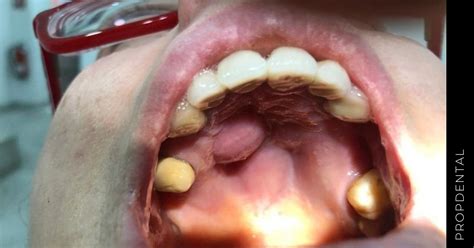

- Torus palatino: Es una protuberancia ósea de apariencia dura. Suele tener una causa genética, es asintomático y no duele.

- Absceso: Es un pequeño bulto o inflamación que se localiza cerca de algún diente.

- Granuloma piogénico: Suele aparecer en mujeres embarazadas y tiende a localizarse en la mitad del paladar. Se trata de un abultamiento rosado, blando y de consistencia fina. Además, si se irrita puede llegar a sangrar.

- Mucocele: Se genera por la acumulación de moco o por una alteración de las glándulas salivales del paladar. Se trata de un bulto blando, inflamado y con crecimiento muy lento. En algunas ocasiones, llega a desaparecer por sí solo.

- Adenoma pleomorfo: Es un tumor benigno de las glándulas salivales. Se manifiesta mediante un bulto o masa que se localiza, normalmente, a los lados de la línea media del paladar. Tiene un crecimiento muy lento y, además, no resulta doloroso.

- Tumor maligno: Se presenta como un abultamiento similar al anterior. Sin embargo, tiene un crecimiento mucho más rápido y doloroso. De todos los tipos mencionados, este último es, sin duda, el más complejo de tratar.